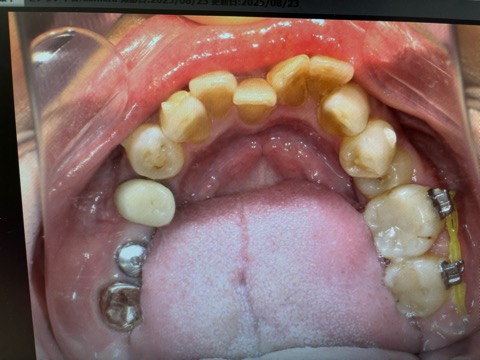

こちらは私の大切なお友達の下の歯のお写真です。女優さん並みに綺麗な方なのに、下の歯がガチャガチャしていて、近所の矯正の先生に診ていたいていたのがなかなか治療が進みませんでした。

この時点ですでに2年が経過していました。奥歯がなかなか動かず、埋まっていた小臼歯が全く出てきませんでした。